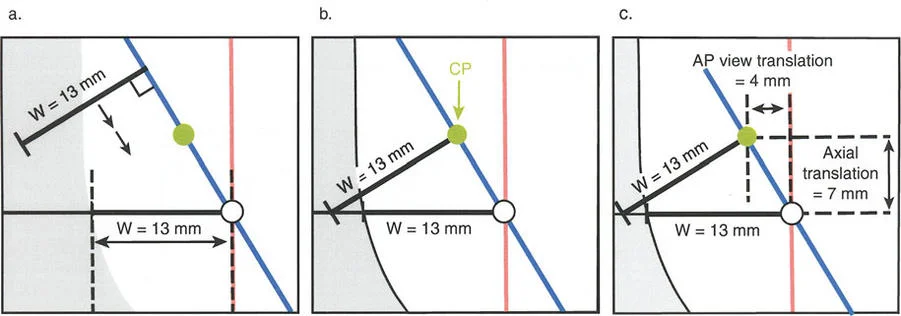

قواعد بالي لقطع العظم (Osteotomy Rules) في وضع الأجهزة

فهم قواعد بالي لقطع العظم أمر لا غنى عنه لتخطيط الإطار:

- قاعدة قطع العظم 1: عندما يمر قطع العظم ومحور تصحيح الانحراف (ACA) كلاهما عبر مركز دوران الانحراف (CORA)، فإن نهايات العظم ستنحرف دون ترجمة (انزياح). يتم استعادة المحور الميكانيكي، وتظل نهايات العظم متقاربة تمامًا، مما يخلق تصحيحًا كلاسيكيًا "إسفينيًا مفتوحًا" أو "إسفينيًا مغلقًا".

- قاعدة قطع العظم 2: عندما يمر محور تصحيح الانحراف (ACA) عبر مركز دوران الانحراف (CORA)، ولكن يتم إجراء قطع العظم على مستوى مختلف (غالبًا بسبب ضعف جودة العظم عند CORA أو مشاكل في الجلد)، فإن نهايات العظم ستنحرف وتخضع لترجمة محسوبة ومقصودة لإعادة محاذاة المحور الميكانيكي.

- قاعدة قطع العظم 3: (للاكمال) عندما يمر قطع العظم عبر مركز دوران الانحراف (CORA)، ولكن يتم وضع محور تصحيح الانحراف (ACA) خارج CORA، سيتم إنشاء تشوه ترجمة جديد، وهو خطأ شائع في وضع المفصلات غير المخطط له جيدًا.

في المنشآت القريبة من المفصل، غالبًا ما نعتمد على قاعدة قطع العظم 2. نظرًا لأنه لا يمكننا قطع العظم بأمان عند خط المفصل تمامًا (مركز دوران الانحراف CORA)، فإننا نقطع العظم في مستوى أدنى في منطقة الميتافيسيس. بعد تحقيق التصحيح الزاوي عبر المفصلات (محور تصحيح الانحراف ACA)، يتم إعادة محاذاة خطوط المحور الميكانيكي بشكل مثالي، ولكن نهايات العظم في موقع قطع العظم تتحرك بالنسبة لبعضها البعض.